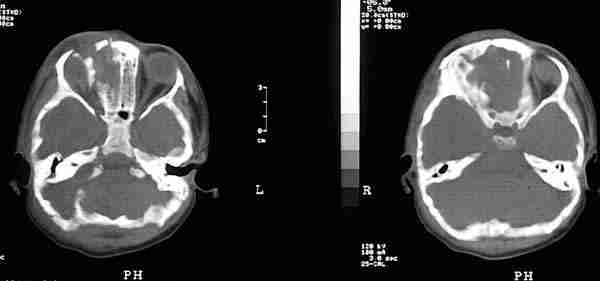

La utilización de Rayos X (figura 15) con proyecciones Caldwell, Waters, o las antero-posteriores pueden demostrarnos la presencia, pero no la localización, de un CEIO radiopaco y no detectará CEIO radiotransparentes, como la madera o el cristal. La ecografía nos ofrece una mejor localización del CEIO y es esencial para obtener información acerca de otros cambios estructurales como desprendimientos de retina o coroides. Al realizar esta exploración, han de tomarse precauciones para no comprimir el globo, sobretodo en los que presentan grandes heridas, y no producir prolapsos adicionales de su contenido. La ecografía con un estudio sistemático, con abordaje transversal y longitudinal puede determinar la localización del CEIO. La ultrasonografía biomicroscópica nos aporta algo más a la hora de diagnosticar cuerpos extraños ocultos o de polo anterior (123-125). La tomografía computerizada (TC) es el método diagnóstico de elección porque localiza y detecta CEIO radiopacos y radiotransparentes en 3 dimensiones. La TC tiene ciertas limitaciones y los CEIO metálicos crean artefactos significativos, que pueden dificultar la localización exacta. Esto puede ser un inconveniente a la hora de determinar si la localización de un CEIO es intrarretiniana o intraescleral. Asímismo la TC puede presentar problemas a la hora de identificar algunos CEIO de baja densidad, como la madera. Chacko, nos presenta en su artículo una interesante comparación entre la Tomografía Computerizada clásica (figura 16) y el TAC helicoidal (figura 17), demostrándose esta última más eficaz para la localización espacial de cuerpos extraños intraoculares o intraorbitarios (126).

63-16.jpg (11435 bytes)

Figura 16. Perdigón que pasa a través del ápex orbitario destrozando el nervio óptico.

63-17.jpg (11175 bytes)

Figura 17. La tomografía computerizada (TC) es el método diagnóstico de elección porque localiza y detecta CEIO radiopacos y radiotransparentes en 3 dimensiones.